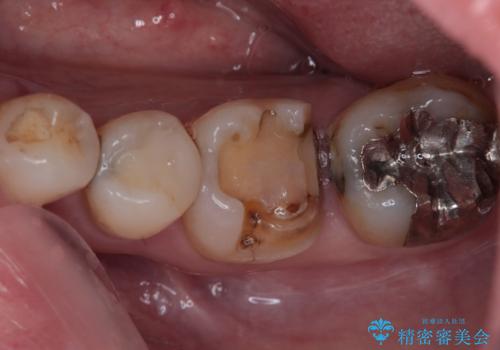

- メタルインレー(保険の金属の詰め物)が取れたとのことで来院された患者様です。

拡大鏡視野下にて、メタルインレーの範囲が大きく虫歯もあったため、オールセラミッククラウンにて修復を行いました。